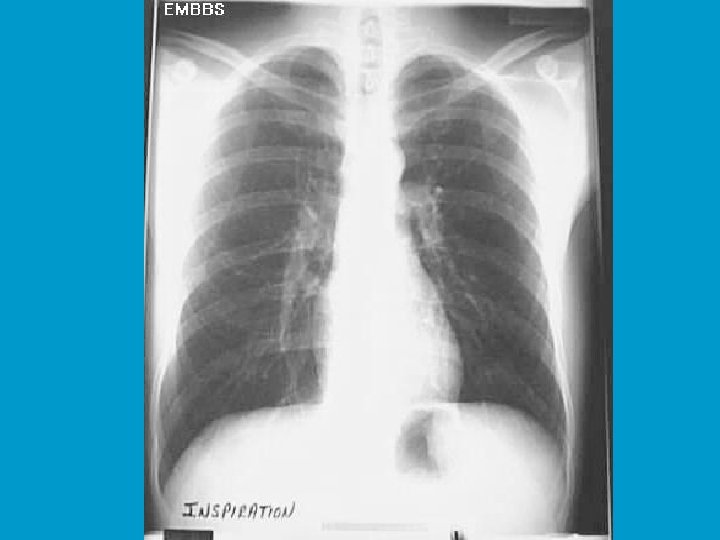

Hodgepodge $200 • A 23 year old female complains of pleuritic chest pain

Hodgepodge $200

Hodgepodge $200 • Hampton’s hump LLL • Pulmonary infarct --> pulmonary embolism • Usually wedge shaped in lung peripherally